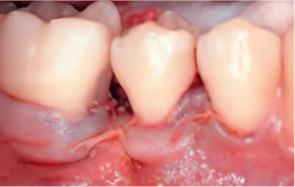

When the gingiva (periodontal tissue) has receded or the alveolar bone has been resorbed, scaling alone has its limits. Gum regeneration therapy regenerates damaged tissue to preserve natural teeth and restore function.

Even when severe periodontal disease has caused gingival recession and alveolar bone resorption, teeth can often be preserved through gum regeneration therapy using Emdogain. This procedure regenerates damaged alveolar bone and surrounding periodontal tissue. By applying Emdogain — a specialized gel that stimulates periodontal tissue regeneration — the supporting structures of the tooth are rebuilt, allowing function and health to be restored without extraction.

Emdogain Surgical Procedure

STEP 01

Gingival incision

-

STEP 02

Scaling and Root Planing (SRP)